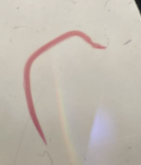

Schistosoma adult worms (male and female)

What sex?

Male Schistosoma

Female Schistosoma